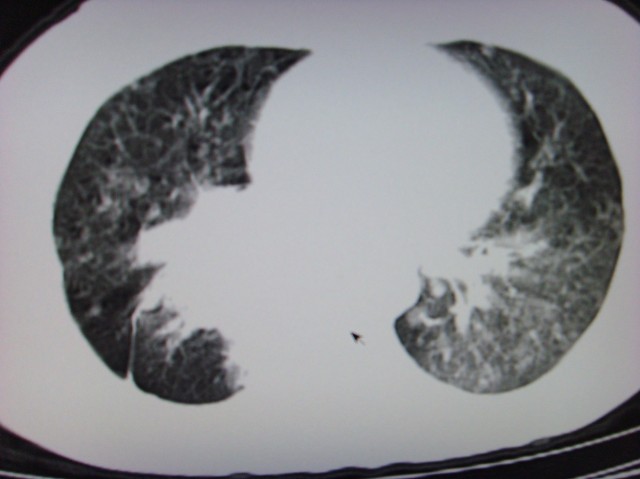

标题: CT7125:中央性肺Ca. [打印本页]

标题: CT7125:中央性肺Ca.

典型 中央型ca伴双肺、淋巴结转移

典型 中央型ca伴双肺、淋巴结、胸膜转移

右下中心型肺癌伴双肺转移、纵隔淋巴结转移,癌性淋巴管炎可能性大

支持楼主的中央型肺癌,肺内,纵隔内淋巴结转移

典型的中央型ca伴双肺、纵隔淋巴结转移.

支持楼主诊断:中央型肺癌,肺内,纵隔内淋巴结转移。

典型--右下中心型肺癌伴双肺转移、纵隔淋巴结转移,癌性淋巴管炎可能性大

中心型肺癌伴双肺转移及纵隔淋巴结转移,癌性淋巴管炎

典型的中央型ca,肿快和肺门分界不清,肿快边界模糊,呈毛刺状。伴淋巴结转移。

首先考虑中央型肺癌伴阻塞性肺炎双肺、淋巴结转移,可以正规抗炎治疗一周后复查